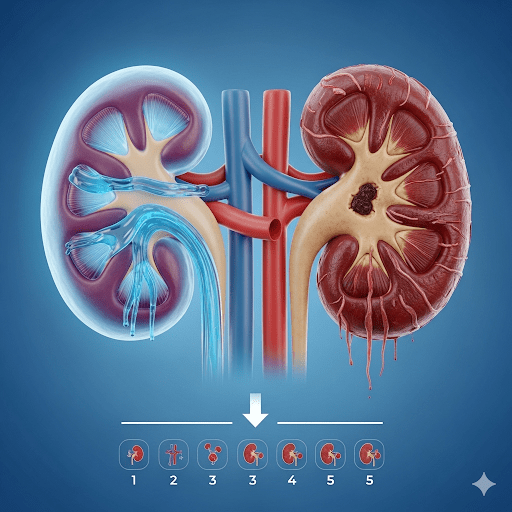

Chế độ ăn uống và tập luyện cho bệnh nhân suy thận theo từng giai đoạn

Suy thận mạn tính (CKD) là tình trạng chức năng lọc của thận suy giảm dần, được chia thành 5…

Suy Thận: Nguyên Nhân, Triệu Chứng và Cách Điều Trị Hiệu Quả

Bạn có biết? Suy thận hiện không còn là “căn bệnh của tuổi già” mà đang ngày càng trẻ hóa…